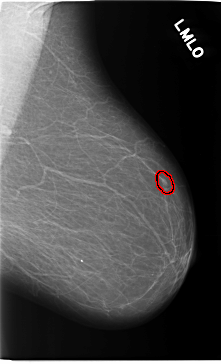

C_0119_1.LEFT_MLO

FILE: C_0119_1.LEFT_MLO.OVERLAY

TOTAL_ABNORMALITIES 1

ABNORMALITY 1

LESION_TYPE MASS SHAPE OVAL MARGINS CIRCUMSCRIBED

ASSESSMENT 4

SUBTLETY 3

PATHOLOGY MALIGNANT

TOTAL_OUTLINES 1

BOUNDARY